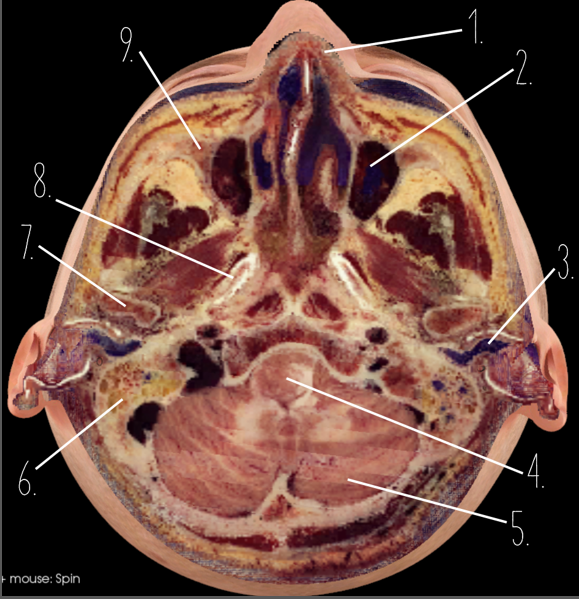

1?

Nasal Bone

2?

Maxillary Sinus

3?

External Acoustic Meatus

4?

Pons

5?

Cerebellum

6?

Mastoid Air Cells

7?

Mandibular Condyles

8?

Sphenoid Bone

9?

Maxillary Bone